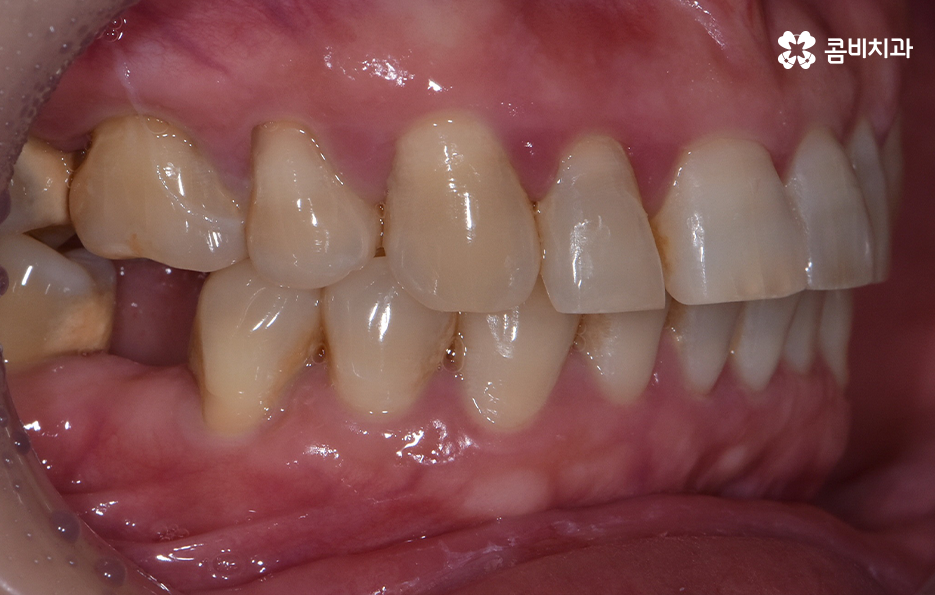

특히 치아가 벌어지거나 삐뚤한 경우에는 임플란트 시술만 한다고 가정할 때 기존의 치열에서 교합 관계 위주로 임플란트의 식립 각도와 위치, 보철물의 크기 등을 결정하게 되지만 치아교정을 통해 가지런한 치열로 개선한 후에 임플란트를 식립하는 경우에는 가지런한 치열을 갖춘 상태에 적합한 임플란트 치료 계획을 세운다는 점에서 이점이 있어요

오늘 보시는 포스팅에서의 치료 과정도 어금니에 임플란트가 필요한 상태에서 윗니를 보시면 윗니가 다소 벌어진 것을 확인할 수 있는데요. 교정 하면 보통 전체교정을 떠올리게 되긴 하지만 경우에 따라서는 치열이 전체적으로 가지런한 편인데 앞니가 살짝 벌어진 경우나 어금니만 다소 벌어진 경우도 있을 거예요

이러한 경우에는 부분교정을 통해서 다소 개선이 필요한 치열을 가지런하게 만들고 가지런해진 치열과 교합 상태에 적합한 임플란트 치료 계획을 세워서 치아의 심미성과 기능적인 부분, 얼굴과의 조화를 종합적으로 고려하여 좋은 결과를 얻을 수 있어요